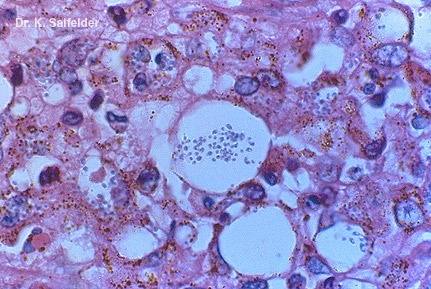

Abb. 9,26: Histoplasmose

Sputum wie in Abb. 9,24 und 9,25. In einer grossen Gewebezelle sind die kleinen Pilzzellen gut zu erkennen. HE-Faerbung